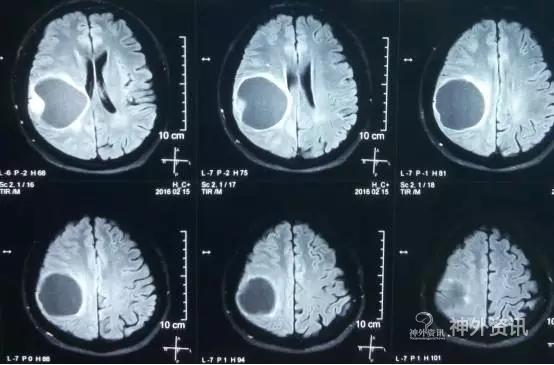

头颅MR示:右颞顶囊性占位伴结节,考虑胶质瘤可能。MRI T1为等信号(图1);T2囊液为高信号(图2);结节为均匀增强(图3);弥散相显示弥散受限(图4)。

图2. T2囊液为高信号。

PXA在CT平扫时表现为低密度囊性病变,境界多较清楚;附壁结节呈稍低密度或等密度,壁结节常紧邻软脑膜;囊性区因含有蛋白或出血,在CT上为略高于脑脊液的液性密度。在MRI上T1W1囊性区呈低信号,壁结节为低或等信号,T2W1为囊性区呈高信号,壁结节为稍高信号。增强扫描可见肿瘤附壁结节明显强化,囊壁可轻度强化或不强化,囊壁强化代表囊壁为肿瘤组织,囊壁不强化说明囊壁为反应性增生的胶质细胞构成。影像学典型表现为囊性病变伴壁结节,少数呈囊实性病变,钙化少见。充分认识这些影像特征有助于提高其诊断及鉴别诊断的准确性,为临床治疗及对预后的判断提供重要的参考价值。少数PXA表现不典型,呈囊实性病变,表现为密度或信号不均匀,增强扫描呈不均匀强化。